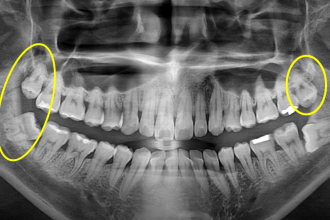

사랑니발치

굿프렌즈 치과 임상 케이스